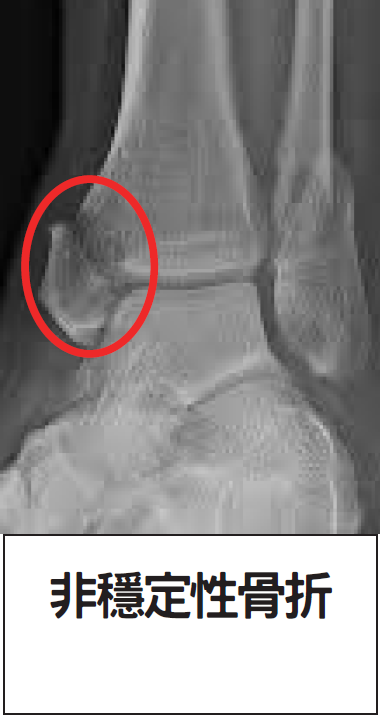

非穩定性骨折: 若骨頭出現裂縫分離或骨折移位(如下圖),則屬非穩定性骨折。